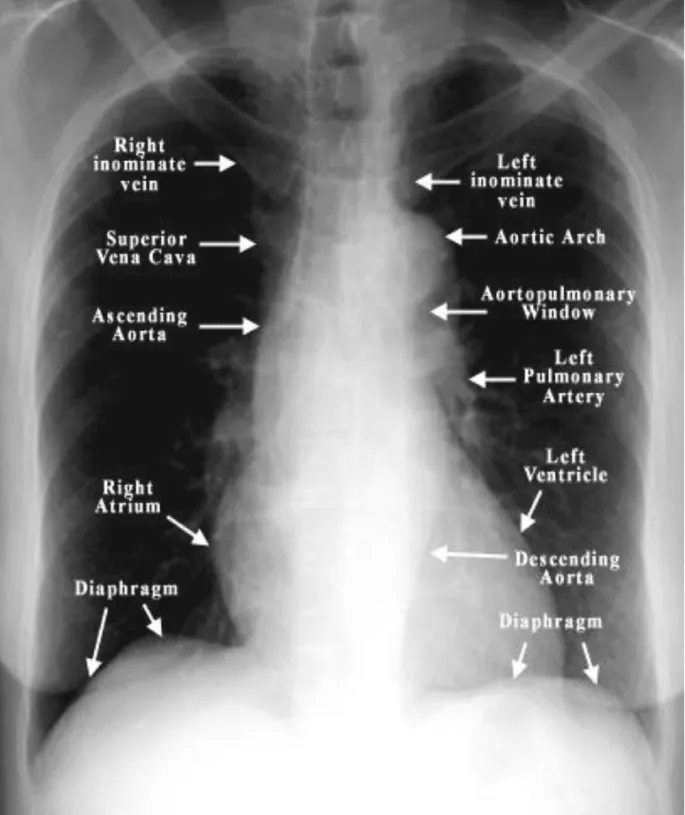

CXR Anatomy & Views - Shadows & Silhouettes

- Standard Views: PA (preferred for minimal magnification), AP, Lateral, Decubitus.

- Systematic Review (ABCDE) 📌:

- Airway: Trachea (midline), carina, main bronchi.

- Bones: Ribs (fractures, lesions), clavicles, scapulae, vertebrae.

- Cardiac/Mediastinum: Cardiothoracic Ratio (CTR) < 0.5 (PA view). Assess size, contours (aortic knob, main pulmonary artery).

- Diaphragm: Right hemidiaphragm higher than left. Sharp costophrenic angles.

- Everything Else/Fields: Lung zones, vascularity, pleura (effusions, pneumothorax), soft tissues.

- Silhouette Sign: Loss of border between structures of same radiographic density (e.g., fluid, soft tissue); indicates lesion is anatomically contiguous with that structure.

⭐ Silhouette Sign: Right middle lobe (RML) pneumonia typically obscures the right heart border on a PA CXR because the RML is anterior and adjacent to the right heart border.